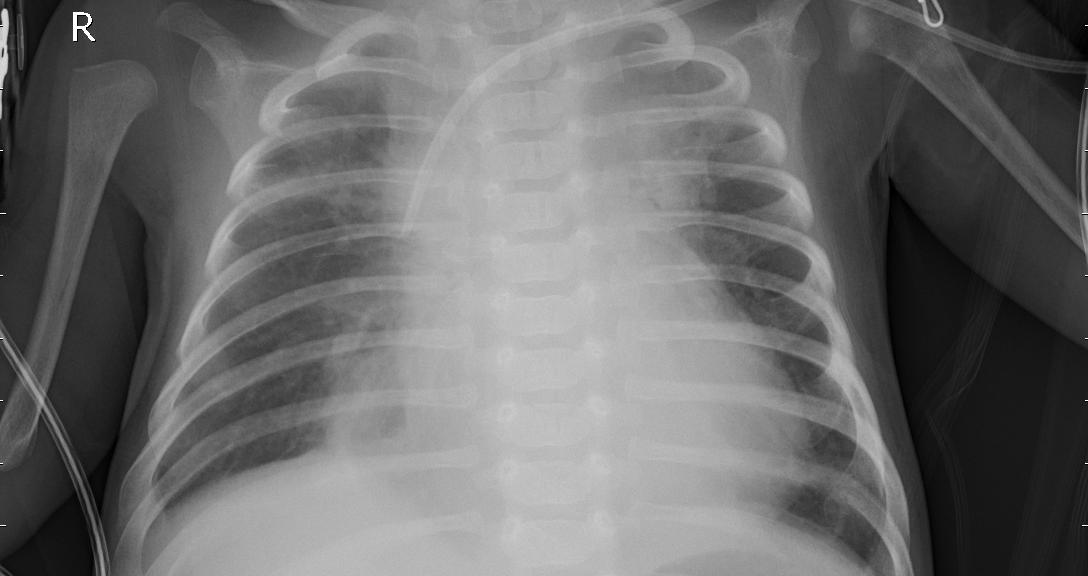

3.2 Sample Chest X-Ray Images

To illustrate the dataset, Fig. 1 shows two representative chest X-ray images from the test set. The first image corresponds to a pneumonia-affected lung, while the second image represents a normal chest X-ray. These examples highlight the visual contrast between infected and healthy lungs that the model aims to classify.